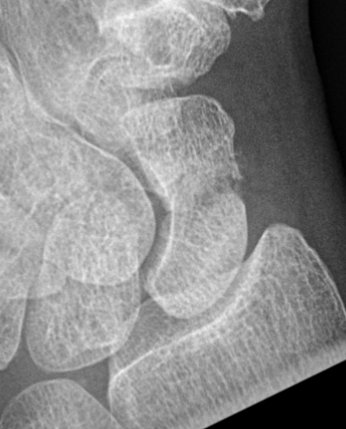

Scaphoid waist fracture 1 mm displaced

Scaphoid fracture with significant displacement

Scaphoid proximal pole fracture